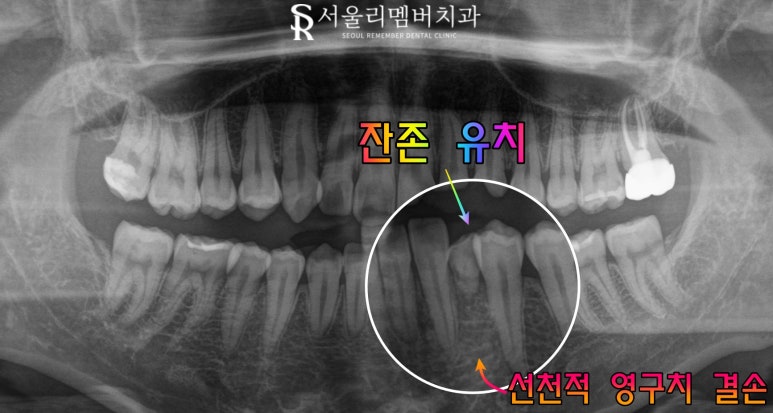

실제 서울대입구역 치과 에서도

이러한 환자들이 꽤 자주 있기에

이때는 파노라마를 보며

자세한 설명을 드리고 있습니다.

관련 케이스를 보시겠습니다.

오늘 서울대입구역 치과 에서

이해를 돕기 위해 준비한 케이스에서는

좌측 하악 부위에

유치가 남아있는 상황이었습니다.